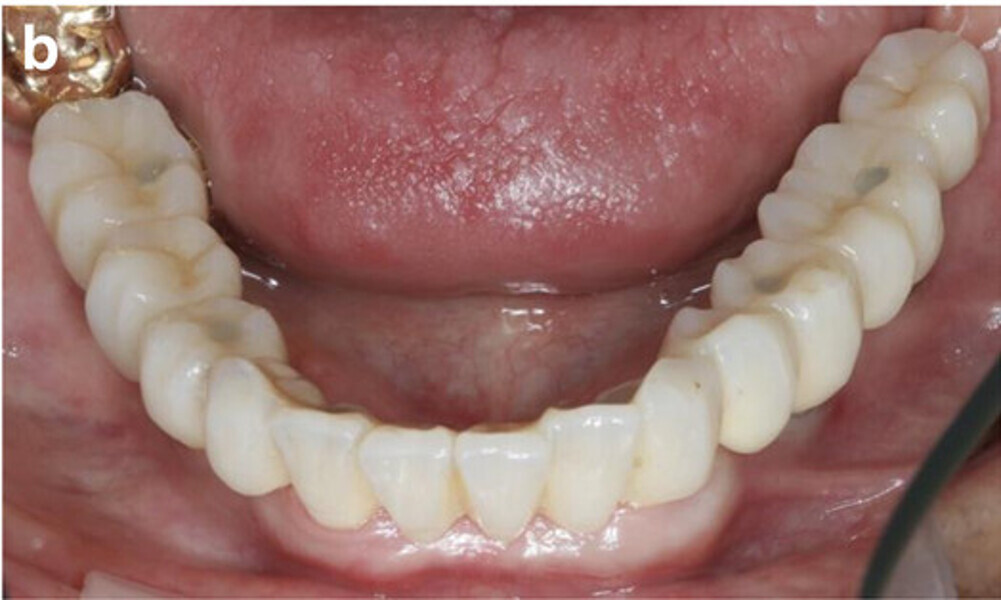

Fig. 14a: Occlusal, frontal and lateral views on the day of delivery, showing healthy peri-implant mucosal conditions (a) and the final CAD/CAM restoration in situ (b–e).

Fig. 14b: Occlusal, frontal and lateral views on the day of delivery, showing healthy peri-implant mucosal conditions (a) and the final CAD/CAM restoration in situ (b–e).

Fig. 14c: Occlusal, frontal and lateral views on the day of delivery, showing healthy peri-implant mucosal conditions (a) and the final CAD/CAM restoration in situ (b–e).

Fig. 14d: Occlusal, frontal and lateral views on the day of delivery, showing healthy peri-implant mucosal conditions (a) and the final CAD/CAM restoration in situ (b–e).

Fig. 14e: Occlusal, frontal and lateral views on the day of delivery, showing healthy peri-implant mucosal conditions (a) and the final CAD/CAM restoration in situ (b–e).